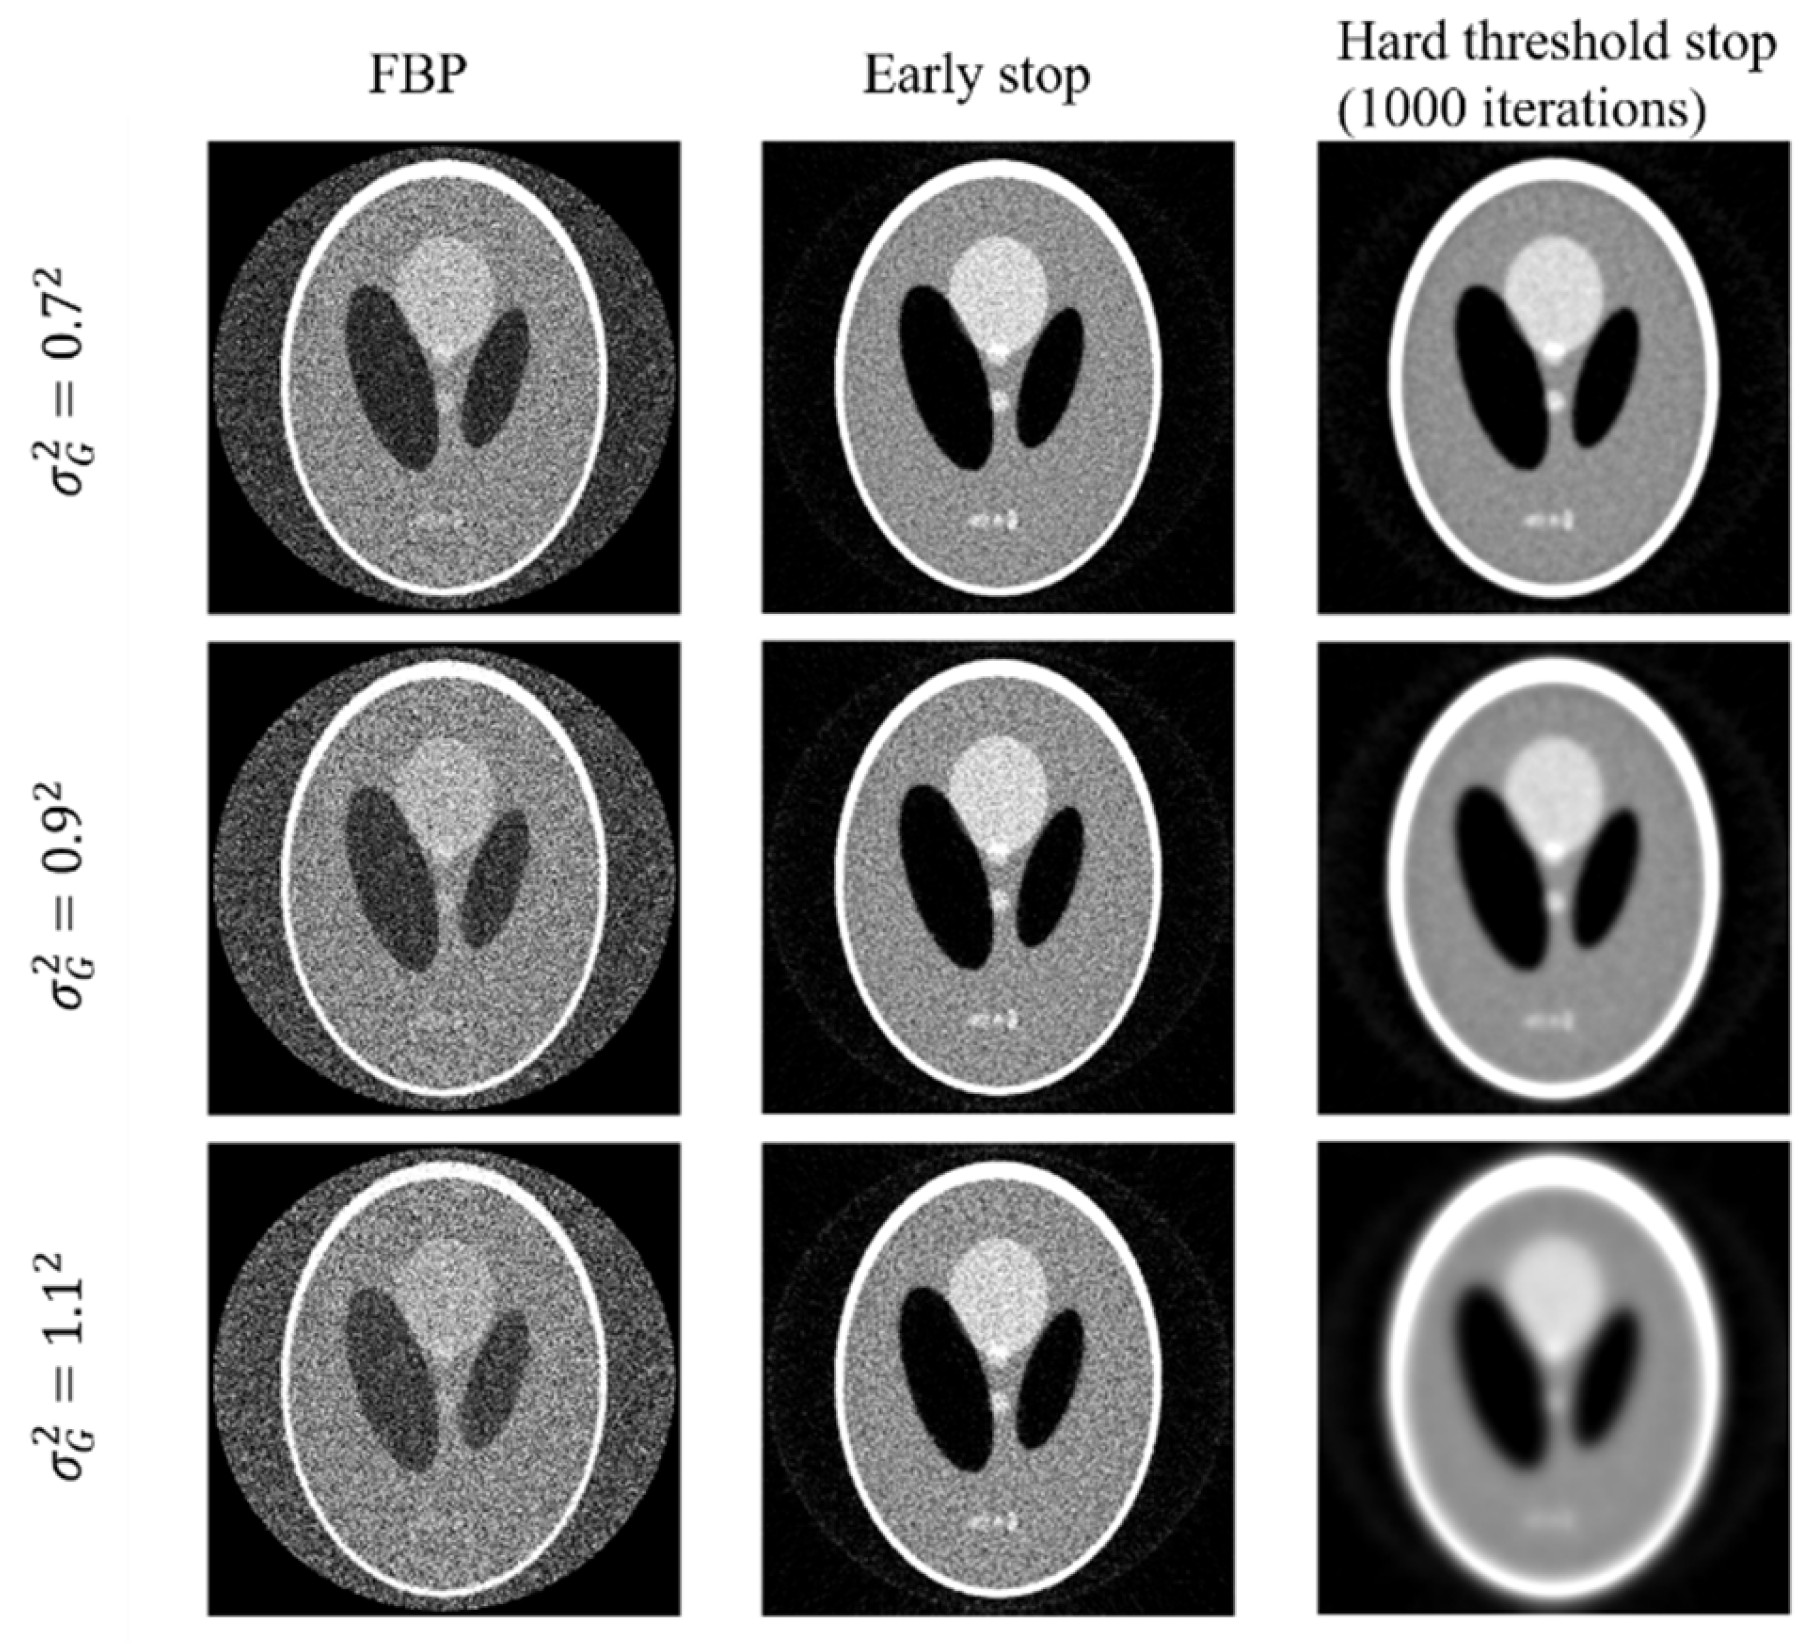

In the experiments, it is noticed that the stopping criterion should be part of the joint-parameter-Bayes method. Ignoring the stopping criterion may result in unsatisfying results. We presented the reconstructed images of early stop criterion and hard threshold in Figure 5. We can see that the early stop can produce better reconstructed images.

Figure 5.

Reconstructed images by FBP (left column) and the joint-parameter-Bayes method with early stop (middle column) and hard threshold stop (right column). The display window is [0, 0.035] mm−1.